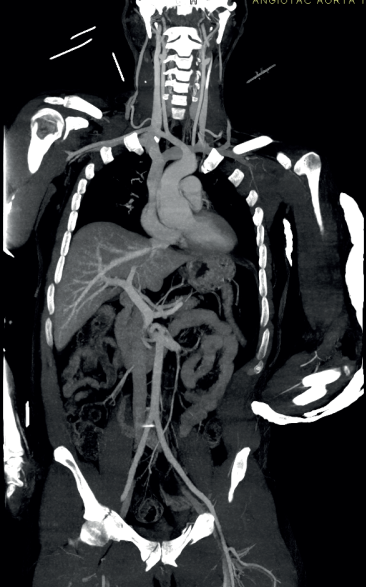

Lo anterior demuestra que, cuando esta herramienta está disponible a la cabecera del paciente en un centro de trauma, si se utiliza con criterios clínicos adecuados y bajo la supervisión de un equipo multidisciplinario que incluya medicina de emergencias, radiología y cirugía de trauma y emergencias, es posible que haya disponibilidad de todas las herramientas necesarias para hacer una evaluación detallada y rápida, en especial, de los pacientes que representan un reto diagnóstico, esto es, con politrauma e inestabilidad hemodinámica (figura 1).